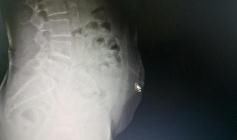

文章插图

影像显示阿婆断针的位置